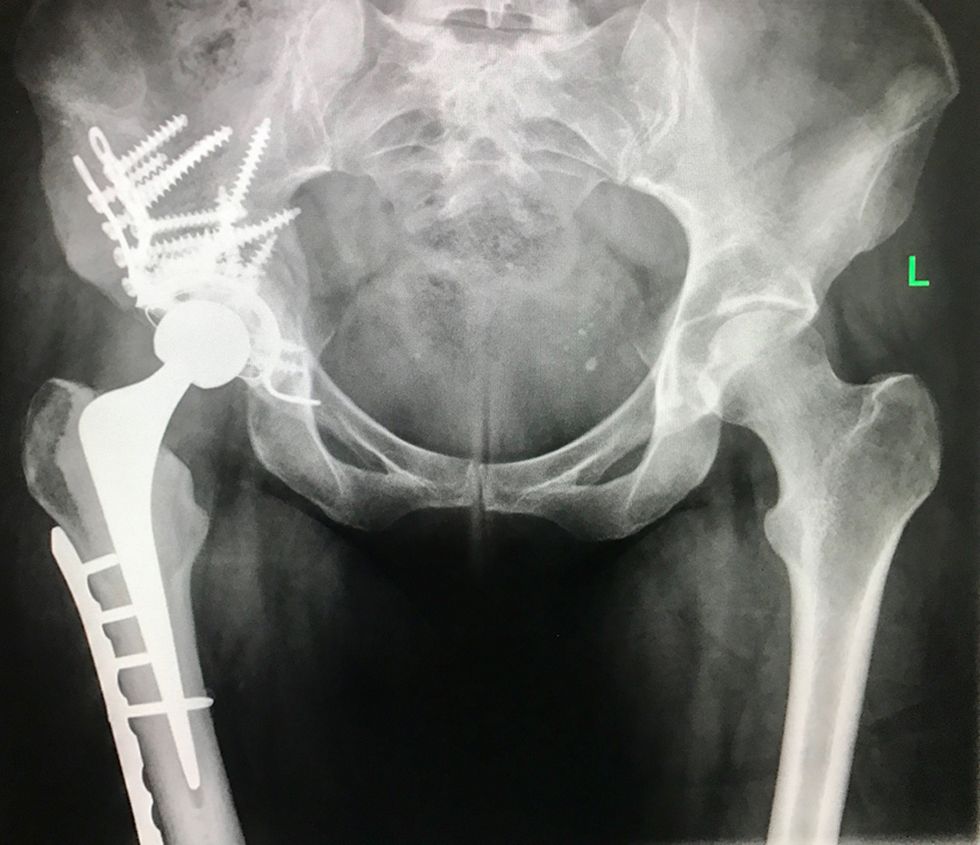

Thankfully, orthopaedic surgeons at Royal Devon and Exeter Hospital were able to operate in the end.

In April 2017, she had a full hip replacement and bone graft. Then she had a metal plate and mesh cage fitted to strengthen her limb.

“I'm still not fully recovered from that. I progressed from walking with a frame, to two crutches, to one, but still need regular physiotherapy and bone strengthening treatment. I'm continuing to have hormone treatment, too, but because I'm classed as stage four, it's more to keep the cancer at bay than to cure it.